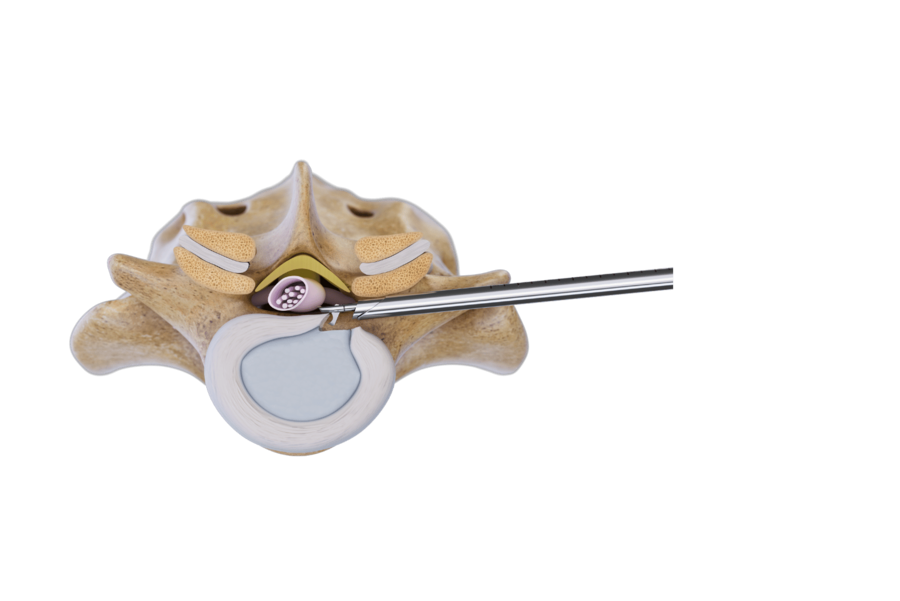

椎間孔アプローチは、脊柱管内および椎間板と同様に、椎間孔および椎間孔外の脊椎病変を治療するための低侵襲手技です。これにより、最小限の外科的侵襲で直接除圧が可能です。病変に応じて、アプローチには異なる 角度が用いられます:

- 椎間孔内および脊柱管内の病変を治療するための、内外側および経椎間孔アプローチ:角度<20°

- 後外側経椎間孔アプローチ:<45°の角度で、中心性の椎間板病変に最適です。椎間孔が狭い場合は、アクセスを確保するために手動または電動バーを用いた骨切除が必要になる場合があります。

- 腰椎および胸椎部の椎間孔外椎間板ヘルニアおよび椎間孔狭窄を治療するための椎間孔外アプローチ。

外側から後外側への進入角度(20°~30°)を用いて、穿刺カニューレを椎弓根の尾側に固定します。 VERTEBRIS ディスコスコープと器具は、完全内視鏡下で頭側に進められ、椎間板ヘルニアを安全に除去します。